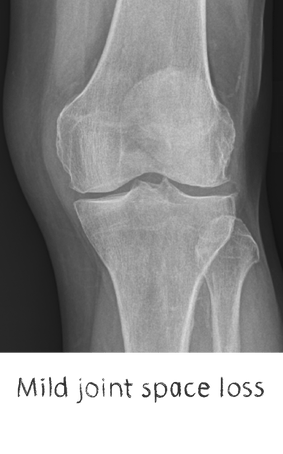

Generally, they all tend to lead to degeneration of the joint, with loss of cartilage, variable bone loss, deformity, stiffness, swelling, and most importantly – PAIN. We commonly call this group – degenerative joint disease

Plain film x-rays are taken to assess the joint

These are usually taken prior to your appointment. These help to confirm the diagnosis, assess the wear pattern and look for particular deformities. They can show old metalware and its position in the bone.